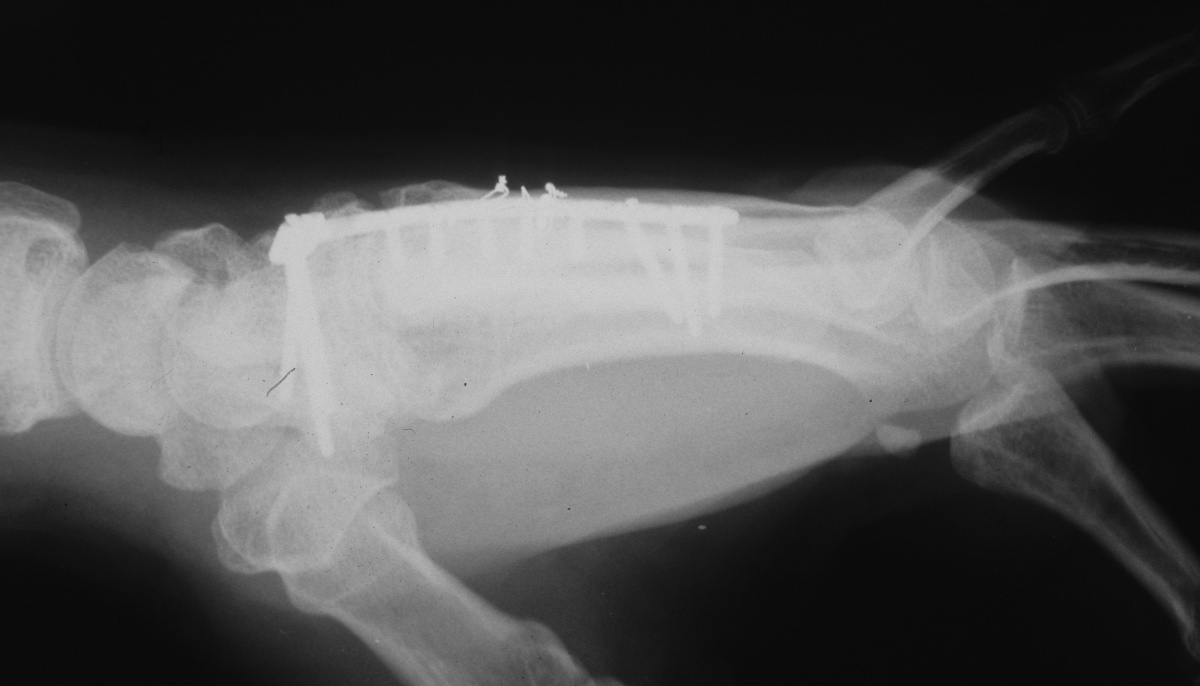

| Three months

postop; bone graft incorporated, active motion

restored, recovery of sensation. |